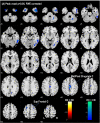

Results: Compared to HC, CD individuals showed decreased gray matter (GM) volumes in frontal and temporal cortices, middle/posterior cingulate cortex, and the cerebellum, at p<0.05, corrected for multiple comparisons. The GM volume of the bilateral superior frontal gyri (SFG) and cingulate cortices were negatively correlated with years of cocaine use, with women showing a steeper loss in the right SFG in association with duration of use. In contrast, the right ventral putamen showed increased GM volume in CD as compared to HC individuals. Compared to HC, CD individuals showed increased fractional amplitude of LFF (fALFF) in the thalamus, with no significant overlap with regions showing GM volume loss.